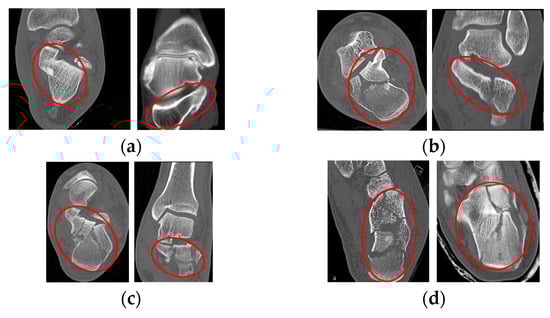

2.5.1. Classification of Calcaneal Fractures in Coronal and Transverse Images

2.5.3. Classification of Calcaneal Fractures in Sagittal Images